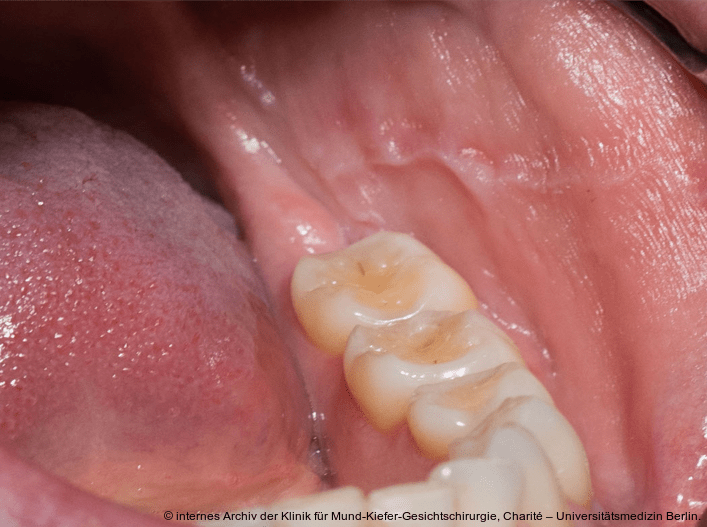

Foto: Klinik für Mund-Kiefer-Gesichtschirurgie, Charité – Universitätsmedizin Berlin

Die Auswirkungen des Sjögren-Syndroms auf die gesundheitsbezogene Lebensqualität sind erheblich.13 Neben der klassischen Sicca-Symptomatik entwickeln viele Patient/-innen systemische Manifestationen wie Arthralgien, Myalgien, neurologische Symptome oder pulmonale Beteiligungen.1, 6 Insbesondere die chronische Fatigue stellt eines der klinisch bedeutsamsten Symptome dar und ist mit einer hohen subjektiven Belastung für die Betroffenen verbunden. Sie ist signifikant mit funktionellen Einschränkungen im beruflichen, sozialen und psychischen Lebensbereich assoziiert.11, 25 Im oralen Bereich kann die persistierende Hyposalivation zu funktionellen Einschränkungen beim Sprechen, Kauen und Schlucken führen.26 Studien zeigen weiterhin ein deutlich erhöhtes Risiko für Karies, Parodontitis und entzündliche oder atrophische Veränderungen der oralen Schleimhäute.1, 24 Da diese Symptome häufig früh im Krankheitsverlauf auftreten, kommt insbesondere der Zahnmedizin und Oralmedizin eine Schlüsselrolle in der Früherkennung des Sjögren-Syndroms zu.6, 27